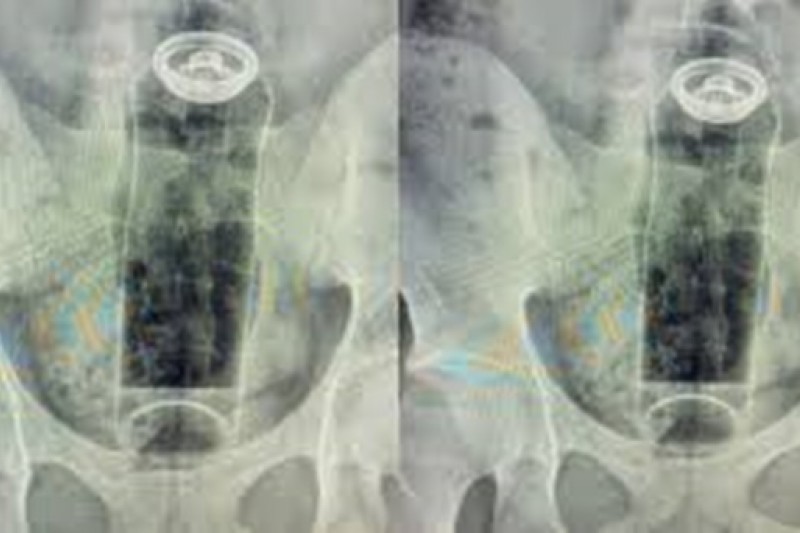

Um jovem de 19 anos precisou ser hospitalizado após um desodorante ficar preso no reto durante uma prática sexual. O caso foi atendido pelo cirurgião coloproctologista Daniel Brosco, que explicou que o objeto acabou sendo “sugado” pelo intestino e não pôde ser retirado em casa, exigindo internação para remoção segura.

Segundo o médico, o paciente relatou que utilizava o desodorante em uma “brincadeira” sexual quando a embalagem subiu para o reto. O episódio levou o especialista a fazer um alerta público nas redes sociais sobre os riscos do uso de objetos inadequados nesse tipo de prática.

O especialista explica que o intestino pode “puxar” objetos introduzidos no ânus devido aos movimentos peristálticos — contrações involuntárias responsáveis pelo funcionamento do órgão — além do efeito de vácuo em regiões como o reto, fazendo com que o item fique preso rapidamente.